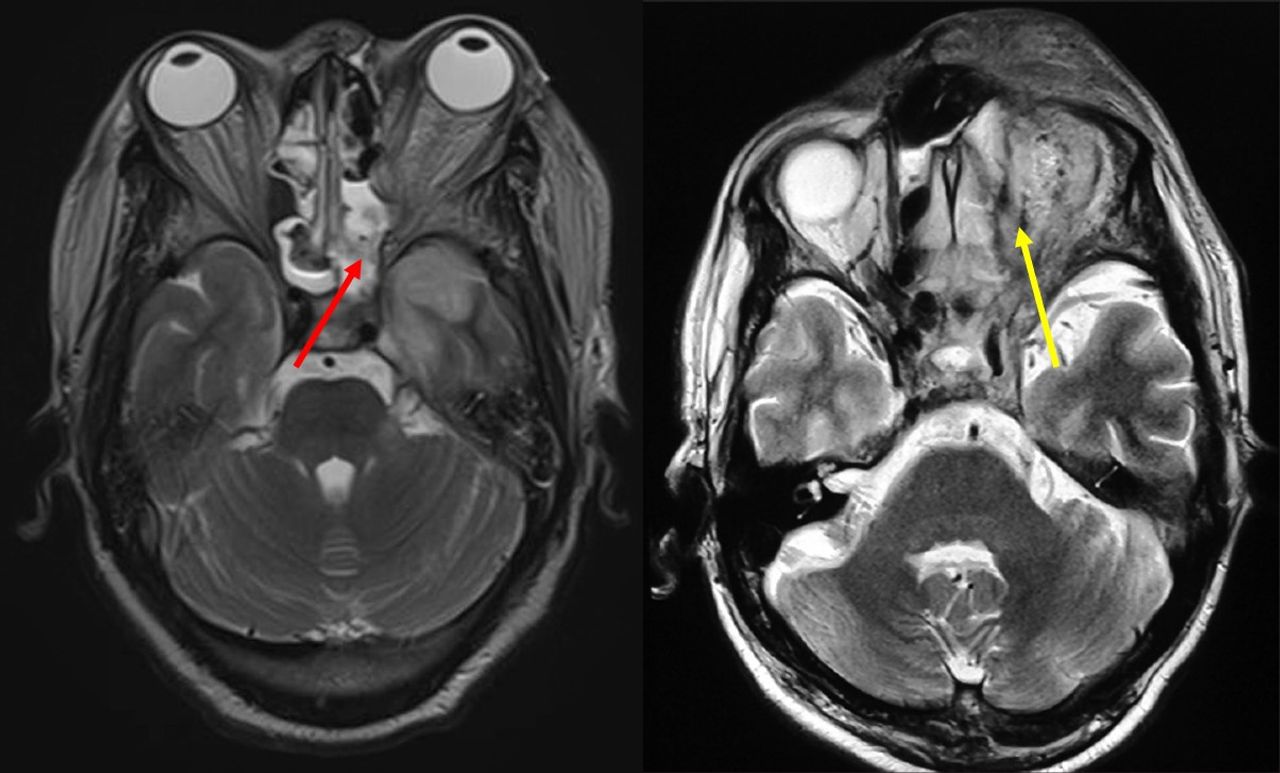

MRI of patients with sinus and orbital abscess with Mucormycosis

Black fungus is a rare but devastating and highly lethal fungal infection if not immediately treated. The disease can fester and spread behind the orbits of the eyes, sinuses and reach the brain, causing the tissue to become necrotic, forming abscesses that need to be surgically resected. If left untreated, these patients can quickly develop metabolic derangements and altered mental activity. The tissue in the nose or palate can die and fall away, causing horrific disfigurement or loss of sight.

The site of the disease—eyes, nose and lungs—is partly because susceptible individuals inhale these spores, and they lodge in the sinuses and lung tissue. In healthy individuals, the cilia that line the tracts of these organs transport them to the gastrointestinal tracts where they are cleared. For those who develop the invasive fungal disease, the hallmark of the infection is the collapse of infected tissue as the fungi invade into the blood vessels leading to tissue damage and death. The term “black fungus” was coined to describe darkened skin lesions in Indian patients who developed this devastating infection after becoming infected with COVID-19.